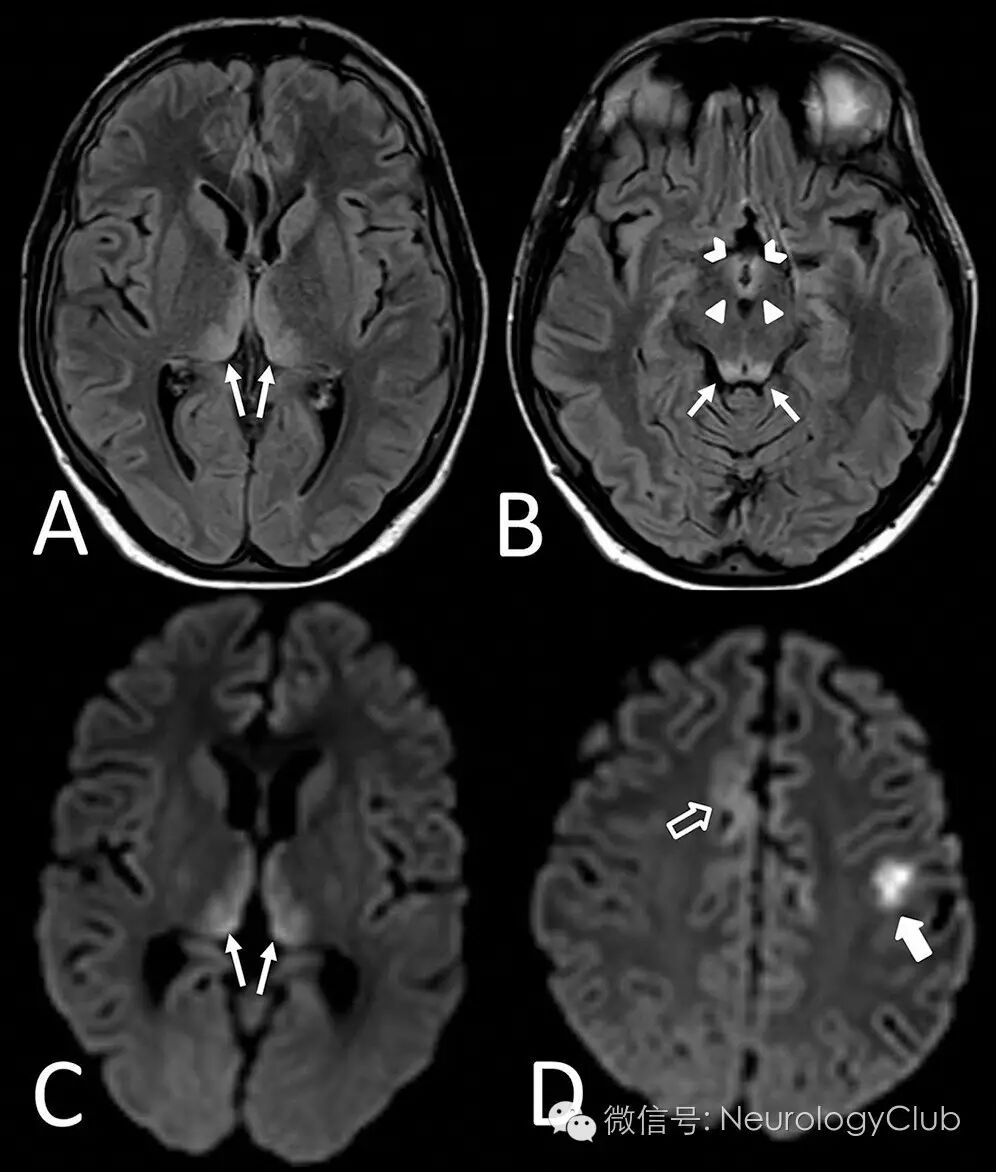

18岁男性患者,既往有浆母细胞淋巴瘤和继发性噬血细胞性淋巴组织细胞增多症并行骨髓移植病史,表现为急性起病的嗜睡,右侧偏瘫和癫痫发作。床边脑电图未见明显异常。T2/FLAIR和DWI提示双侧丘脑内侧面,乳头体,下丘脑,顶盖对称性高信号和弥散受限,左侧旁中央皮层和双侧额叶内侧皮层亦可见病灶(图)。

(图:MRI横断面FLAIR[A-B]和DWI[C-D]提示双侧丘脑内侧面[箭,A,C],乳头体[箭头,B],顶盖[箭,B],下丘脑[V形,B],左侧旁中央皮层[空心箭,D]和右侧额叶内侧皮层[实心箭,D]高信号病灶。DWI高信号病灶在ADC[未给图]上呈低信号,符合弥散受限)